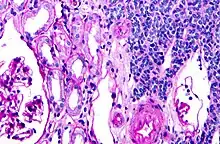

| Micrograph of a metanephric adenoma with structures reminiscent of those seen in papillary renal cell carcinoma. H&E stain. | |

Metanephric adenoma is diagnosed histologically. The tumours can be located at upper pole, lower pole and mid-hilar region of the kidney; they are well circumscribed but unencapsulated, tan pink, with possible cystic and hemorrhagic foci. They show a uniform architecture of closely packed acinar or tubular structures of mature and bland appearance with scanty interposed stroma.[3][4][5][6][7] Cells are small with dark staining nuclei and inconspicuous nucleoli. Blastema is absent whereas calcospherites may be present. Glomeruloid figures are a striking finding, reminiscent of early fetal metenephric tissue. The lumen of the acini may contain otherwise epithelial infoldings or fibrillary material but it is quite often empty. Mitoses are conspicuously absent.[3][4][5][6][7] In the series reported by Jones et al. tumour cells were reactive for Leu7 in 3 cases of 5, to vimentine in 4 of 6, to cytocheratin in 2 of 6, to epithelial membrane antigen in 1 of 6 cases and muscle specific antigen in 1 of 6.[5] Olgac et al. found that intense and diffuse immunoreactivity for alpha-methylacyl-CoA racemase (AMACR) is useful in differentiating renal cell carcinoma from MA but a panel including AMACR, CK7 and CD57 is better in this differential diagnosis.[8] Differential diagnosis may be quite difficult indeed as exemplified by the three malignancies initially diagnosed as MA that later metastasized, in the report by Pins et al.[9]